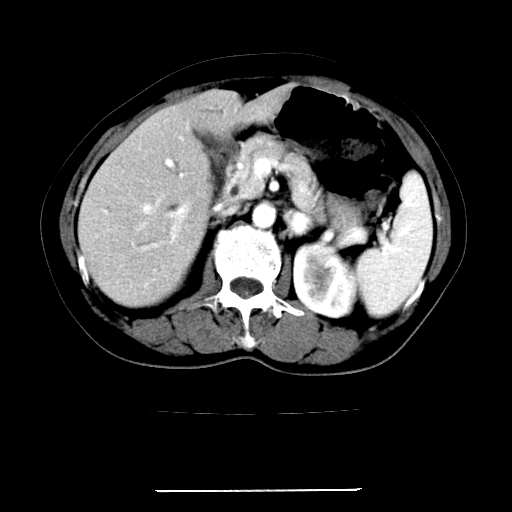

标题: CT22301:女,67岁,上腹部疼痛一周伴皮肤黄染,无发热。 [打印本页]

女,67岁,上腹部疼痛一周伴皮肤黄染,无发热。

考虑:肝内胆管结石继发肝内胆管扩张,右肾旋转不良。

肝内外胆管扩张,左叶胆管内结石

考虑肝胆管癌;胰头占位?【形态失常,体积增大】

1、肝门高密度影下层面和胰头层面可见轻度胆管扩张,而静脉和延迟期均未见扫描完胰头,不能完全排除胰头占位。2、肝门部高密度影,考虑钙化或结石。